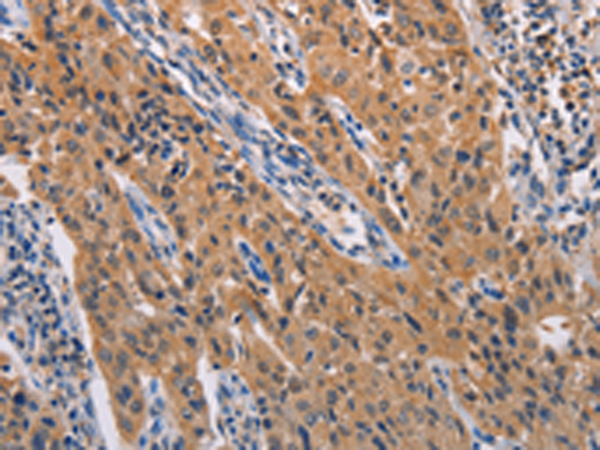

分类: 科研抗体货号: P07798别名: HRB; RAB; RIP应用: WB,IHC反应种属: Human, Mouse, Rat